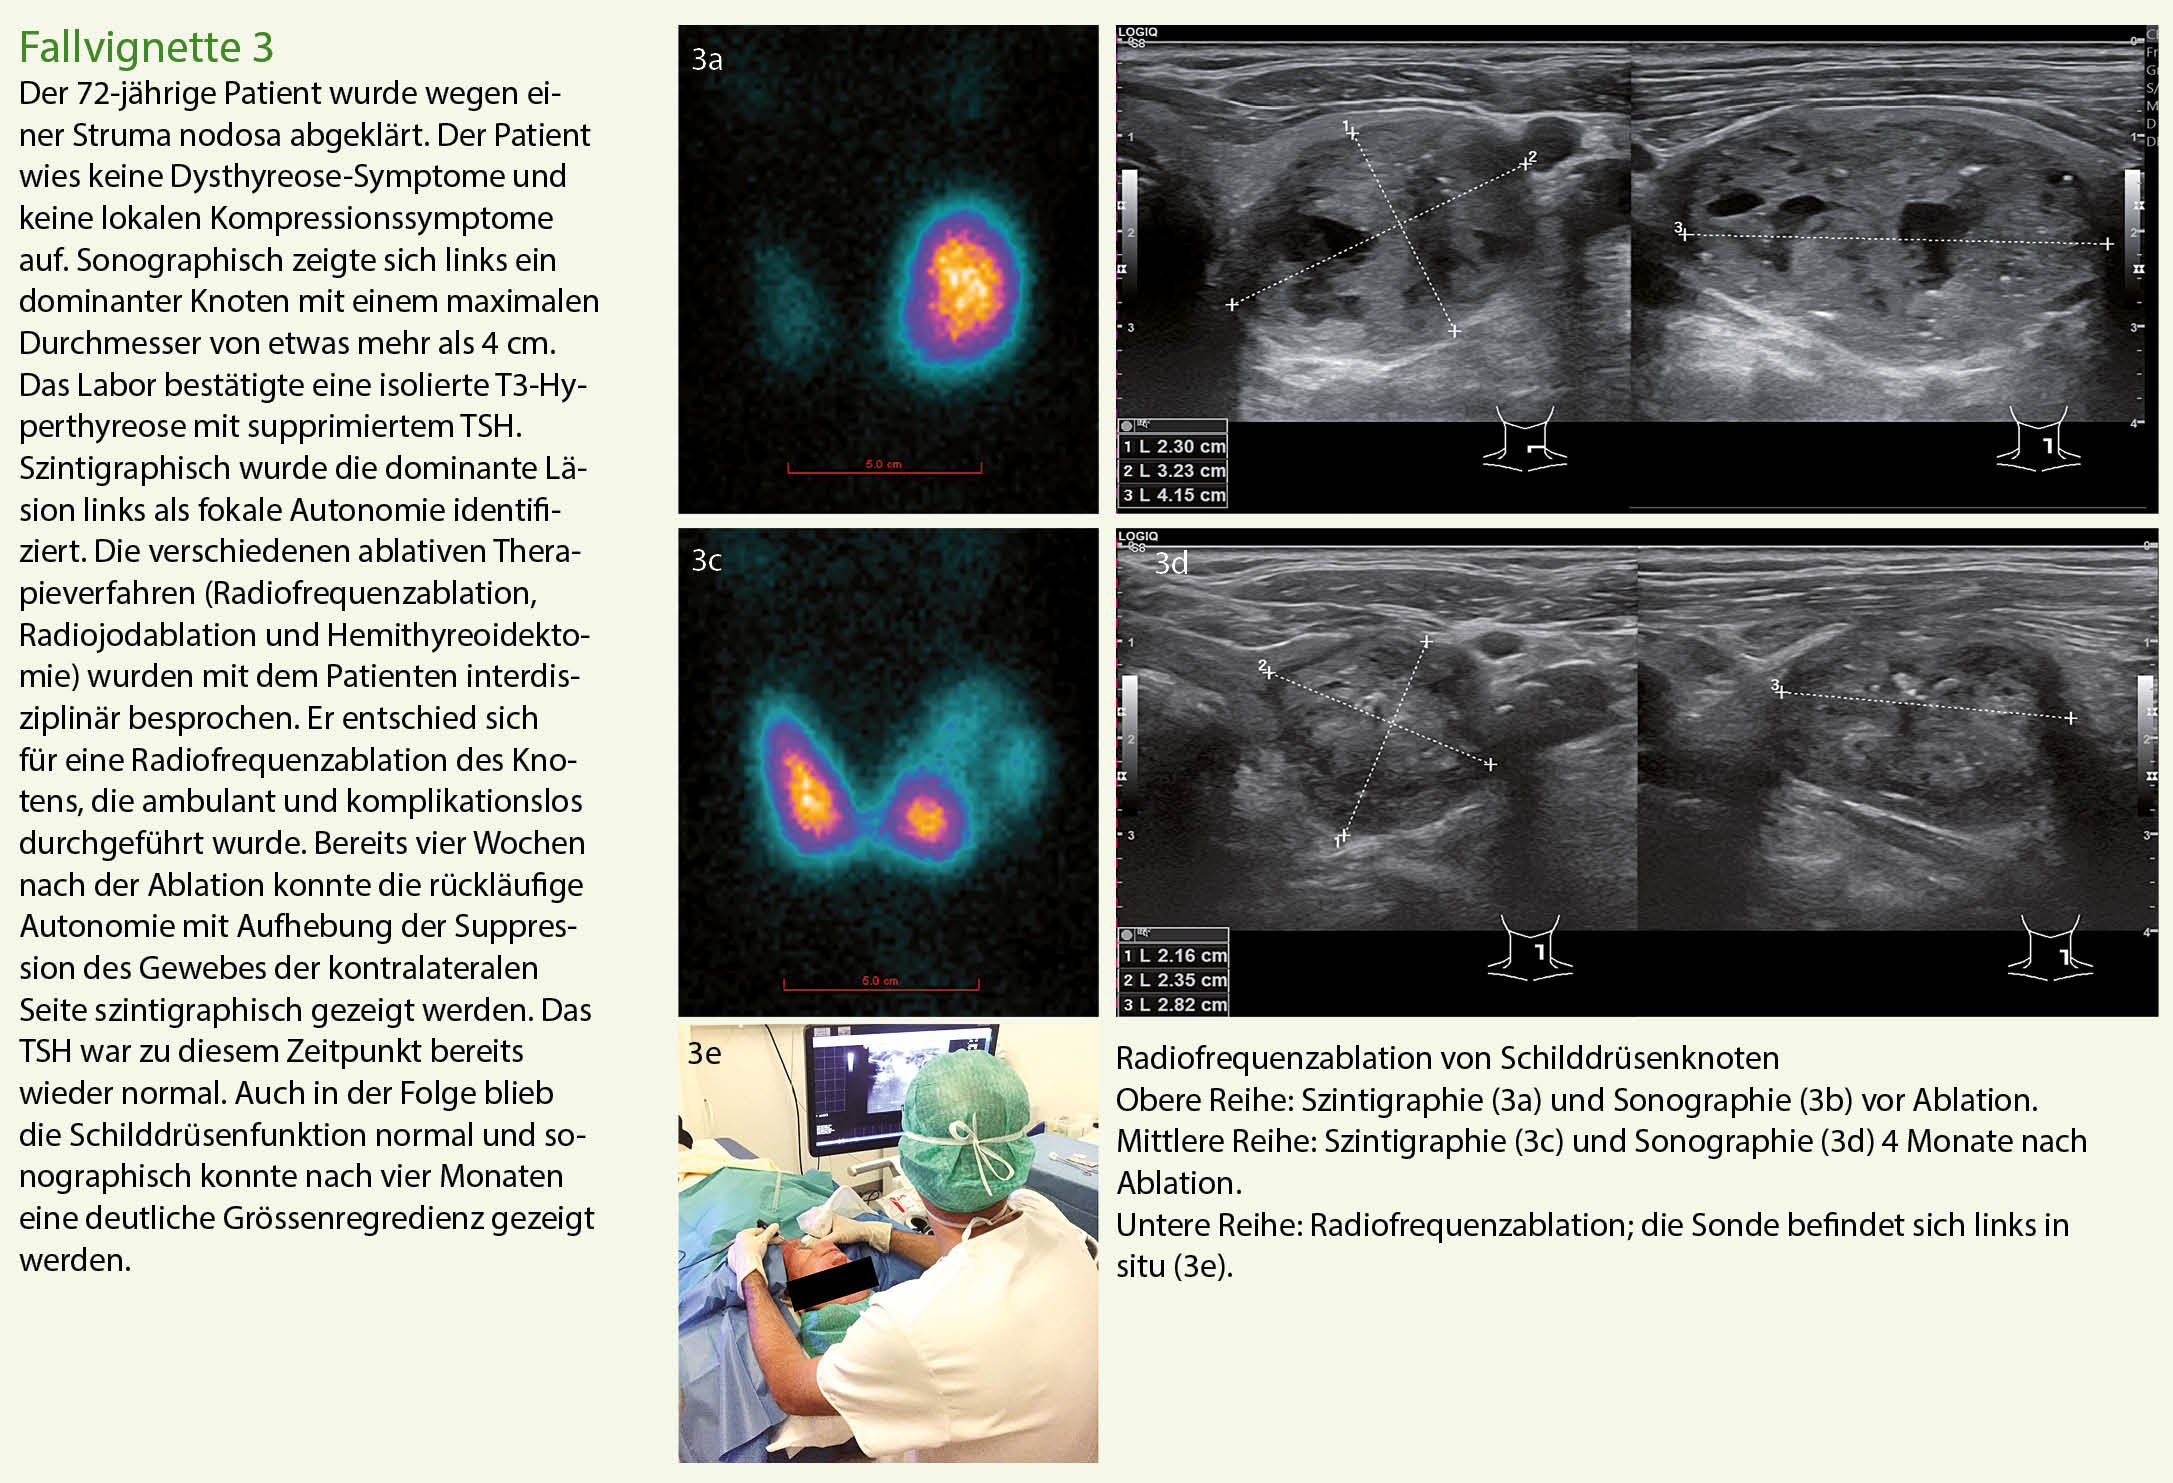

Die Thermoablation

Die ablative Behandlung von unifokalen Autonomien durch Thermoablation mit monopolaren oder bipolaren Sonden stellt ein neueres, minimalinvasives Verfahren dar, das im ambulanten oder kurzstationären Setting durchgeführt wird. Der Vorteil der Methode liegt darin, dass das hyperfunktionelle Gewebe organerhaltend reduziert wird. Die Thermoablation kann zu einer Volumenreduktion von 65-80% führen. Die therapeutische Erfolgsrate in Bezug auf die Normalisierung der Schilddrüsenfunktion reicht von 50 bis fast 90% (9). Die Indikation zur Thermoablation wird in unserem Schilddrüsenzentrum interdisziplinär gemeinsam mit dem Patienten gestellt. Für die Qualitätssicherung werden die Patienten vor und nach dem Eingriff engmaschig kontrolliert (Sonographie, postinterventionelle Szintigraphie zur Beurteilung des Ablationserfolges, prä- und postablationelle phoniatrische Prüfung der Stimmbandfunktion).